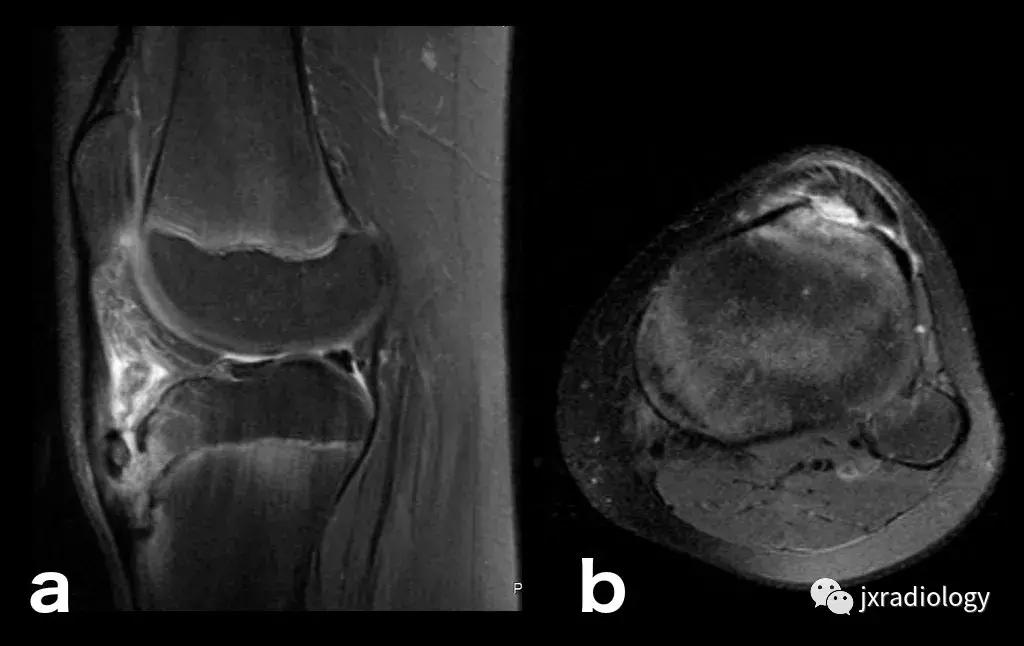

图21:这名患者的炎症性关节炎表现为围绕内侧股 - 胫室侵蚀性改变的骨髓水肿。 它是血管源性骨髓水肿的一个例子(继发于血液和血清传递至骨髓空间毛细血管床)(a,b:冠状T1-WI和PD-FS-WI)。